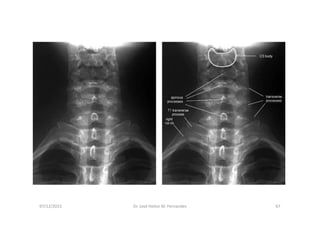

07/12/2015 Dr. José Heitor M. Fernandes 35

RX com a boca aberta mostrando atlas e axis

Anatomia Radiológica Cervical

AP Lateral

07/12/2015 Dr. José Heitor M. Fernandes 66

figura